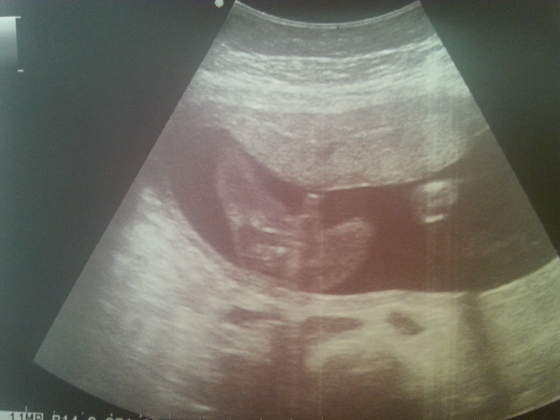

I ja dziś ide na badanie